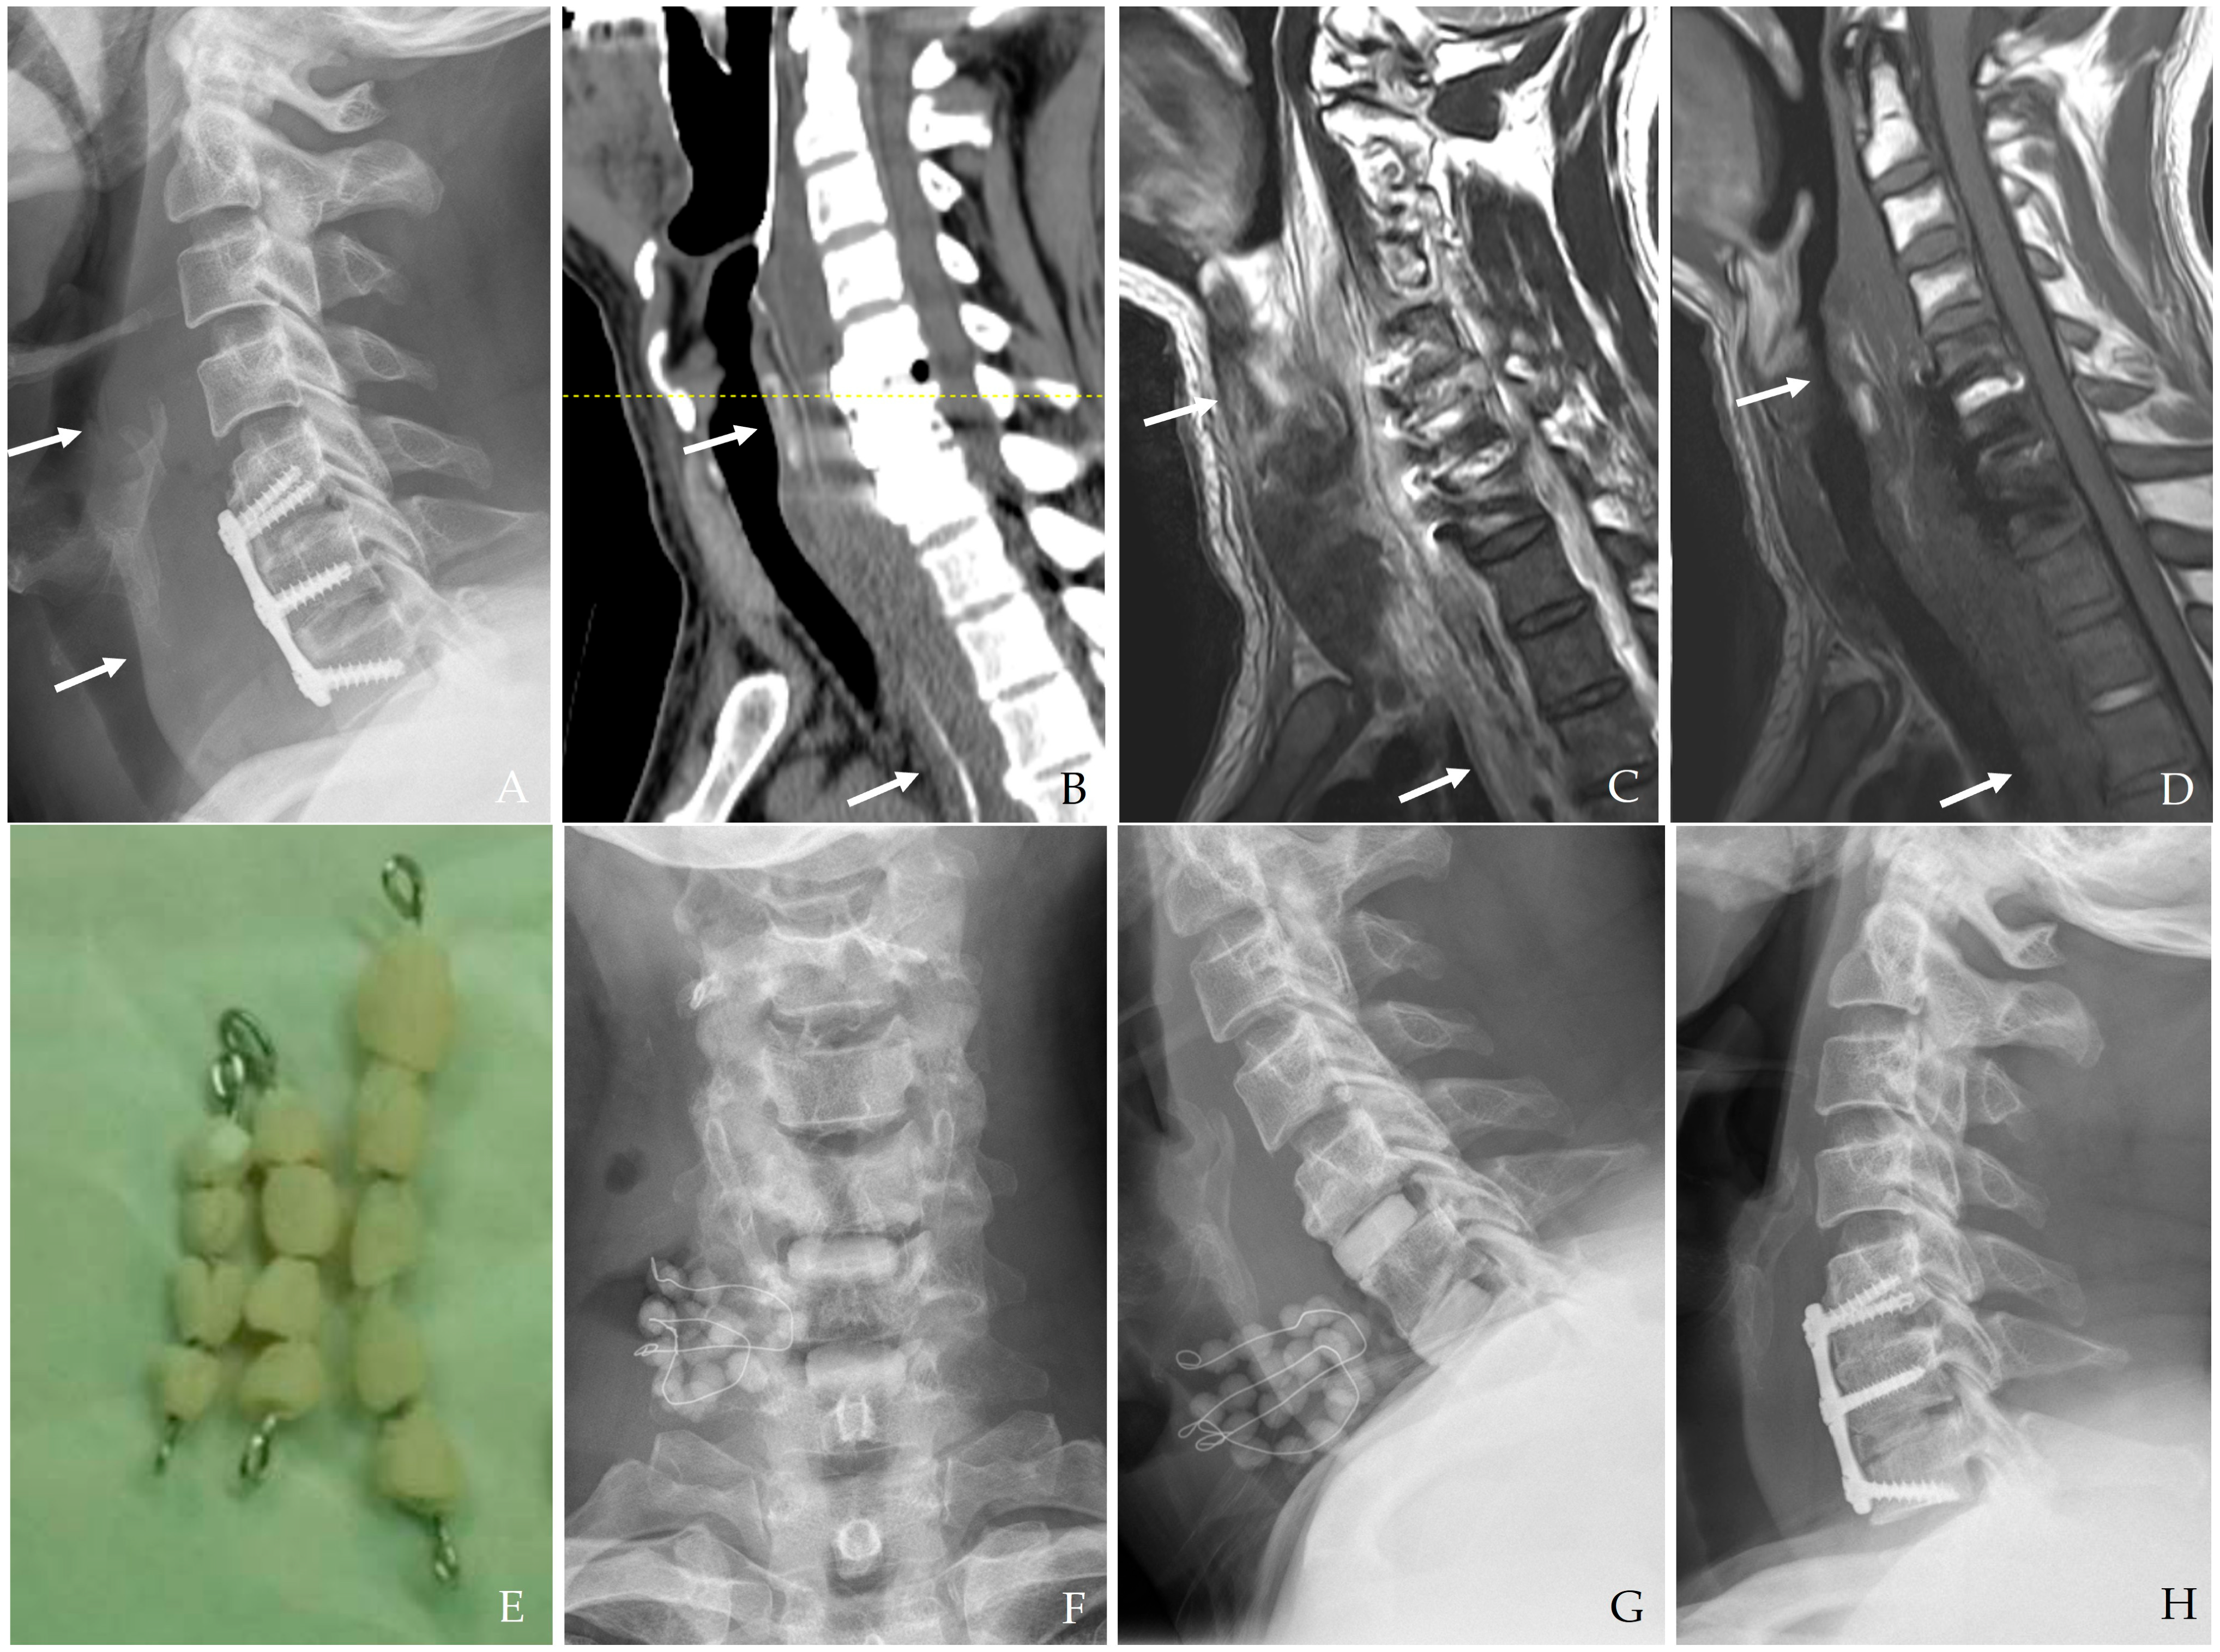

Anterior cervical spine surgery is a critical intervention for a variety of conditions ranging from degenerative disc diseases and traumatic injuries to neoplastic disorders. Although significant improvements have been achieved in surgical techniques, perioperative infection control, and postoperative care, the risk of postoperative infection remains a serious concern [1,2,3]. While the overall incidence of infection in cervical spine surgery is relatively low compared to lumbar procedures due to superior local vascularity and less extensive soft tissue dissection, the anatomical proximity of the cervical spine to vital neurovascular structures and the esophagus creates a high-risk environment for severe complications (Figure 1) [1,2,4,5].

Figure 1. The patient underwent C3-4-5 anterior cervical discectomy and fusion (A). At postoperative 2 months, postoperative infection occurred with retropharyngeal abscess (white arrows) and epidural abscess (B,C). Therefore, the patient underwent evacuation of retropharyngeal and epidural abscesses, irrigation/debridement, and revisional C5-6-7 corpectomy and fusion (D) and achieved a cure for the infection (E).